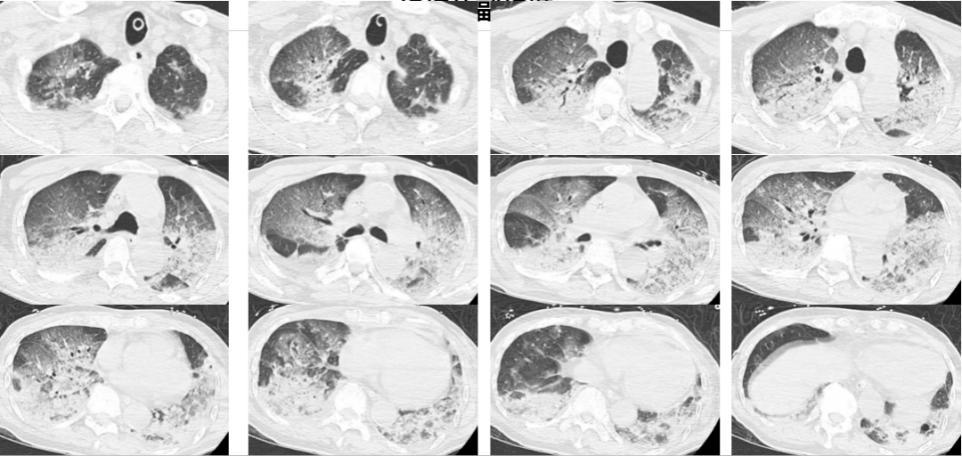

入院時,韓爺爺意識不清,血壓、心率下降,醫生隨即爲他安排頭顱、胸部CT和肺血管CTA檢查,結果顯示,老人的雙肺出現大面積白色影像。經會診,韓爺爺被確診爲熱射病誘發的肺水腫。